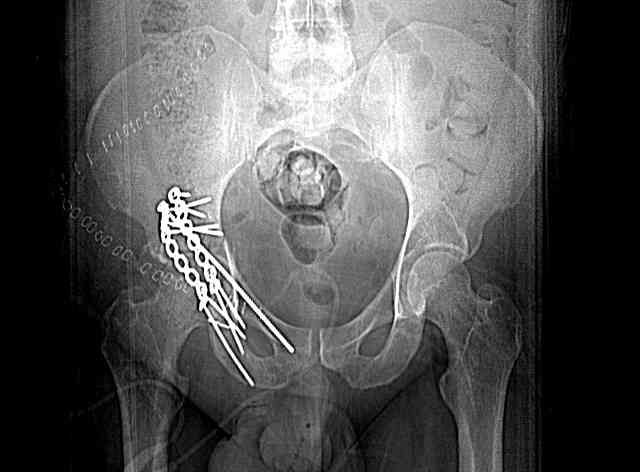

I'll include a few images of a similar injury in a similarly large male patient. This patient "showed up" in our ER c/o hip pain 2 months after being treated in the lateral position, without a quality reduction, without an anterior column transverse supporting implant, with an unbalanced plate applied too medially, with insufficient caudal segment fixation...it took over 8 hours and a 3+ l blood loss to debride the callus from front then

back, excise the HO, release his sciatic nerve, reduce the head-transverse-wall, and fix it...and now it's a staging procedure.